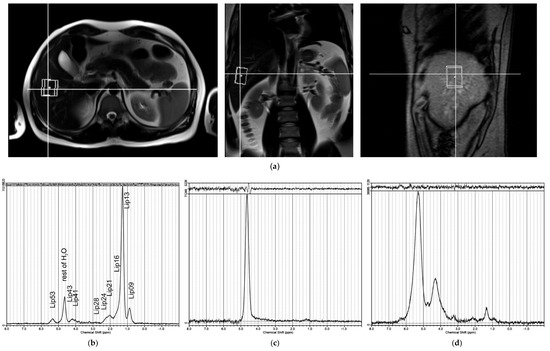

4.3. MR Examination